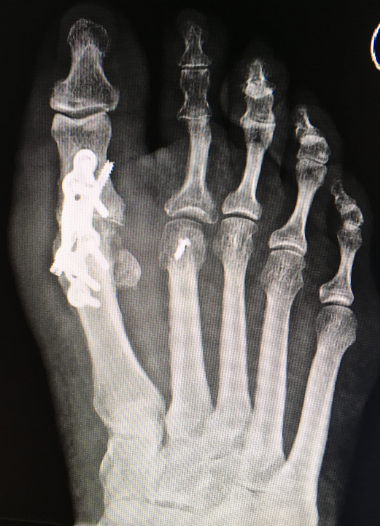

Gesamtes Spektrum der Fuß und Sprunggelenkchirurgie (Plattfuß, Spreizfuß, komplexe Vor-, Mittel- und Rückfußkorrektur, Krallenzehen und Hallux valgus/rigidus, Morton Neurinom)